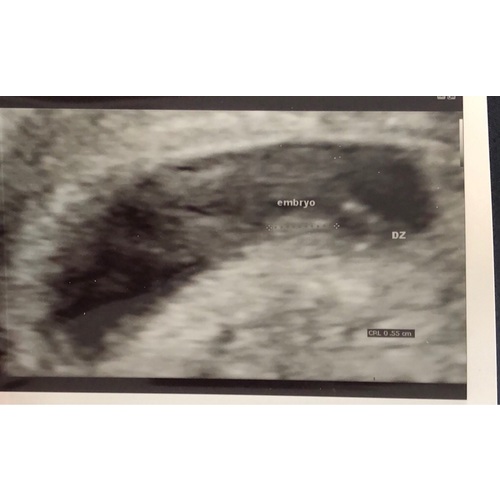

Wij hebben een echo gehad met 6+3 en je zag het hartje mooi kloppen, helaas niet kunnen horen toen. Het is inderdaad heel klein en lijkt helemaal niet op een mini mensje maar er valt wel iets te zien.

Ja wat hieronder al eerder is beschreven, je ziet iets knipperen maar je kan er nog geen mensje uithalen. Gynaecoloog noemde het een rijstkorrel met hartslag haha! Een week later zie je al beginnende armpjes en benen. Wij kregen elke week een echo dus hebben het echt zien groeien, heel bijzonder!

Wij hadden de 1e echo toen ik dacht 7 weken te zijn, dit bleek 5+5 te zijn. Met een inwendige echo het hartje zowel zien als horen kloppen. Verder noemde wij de baby in die weken nog een vlek omdat het eigenlijk niet meer dan dat was... Nu gelukkig al echt een mini mensje :-)